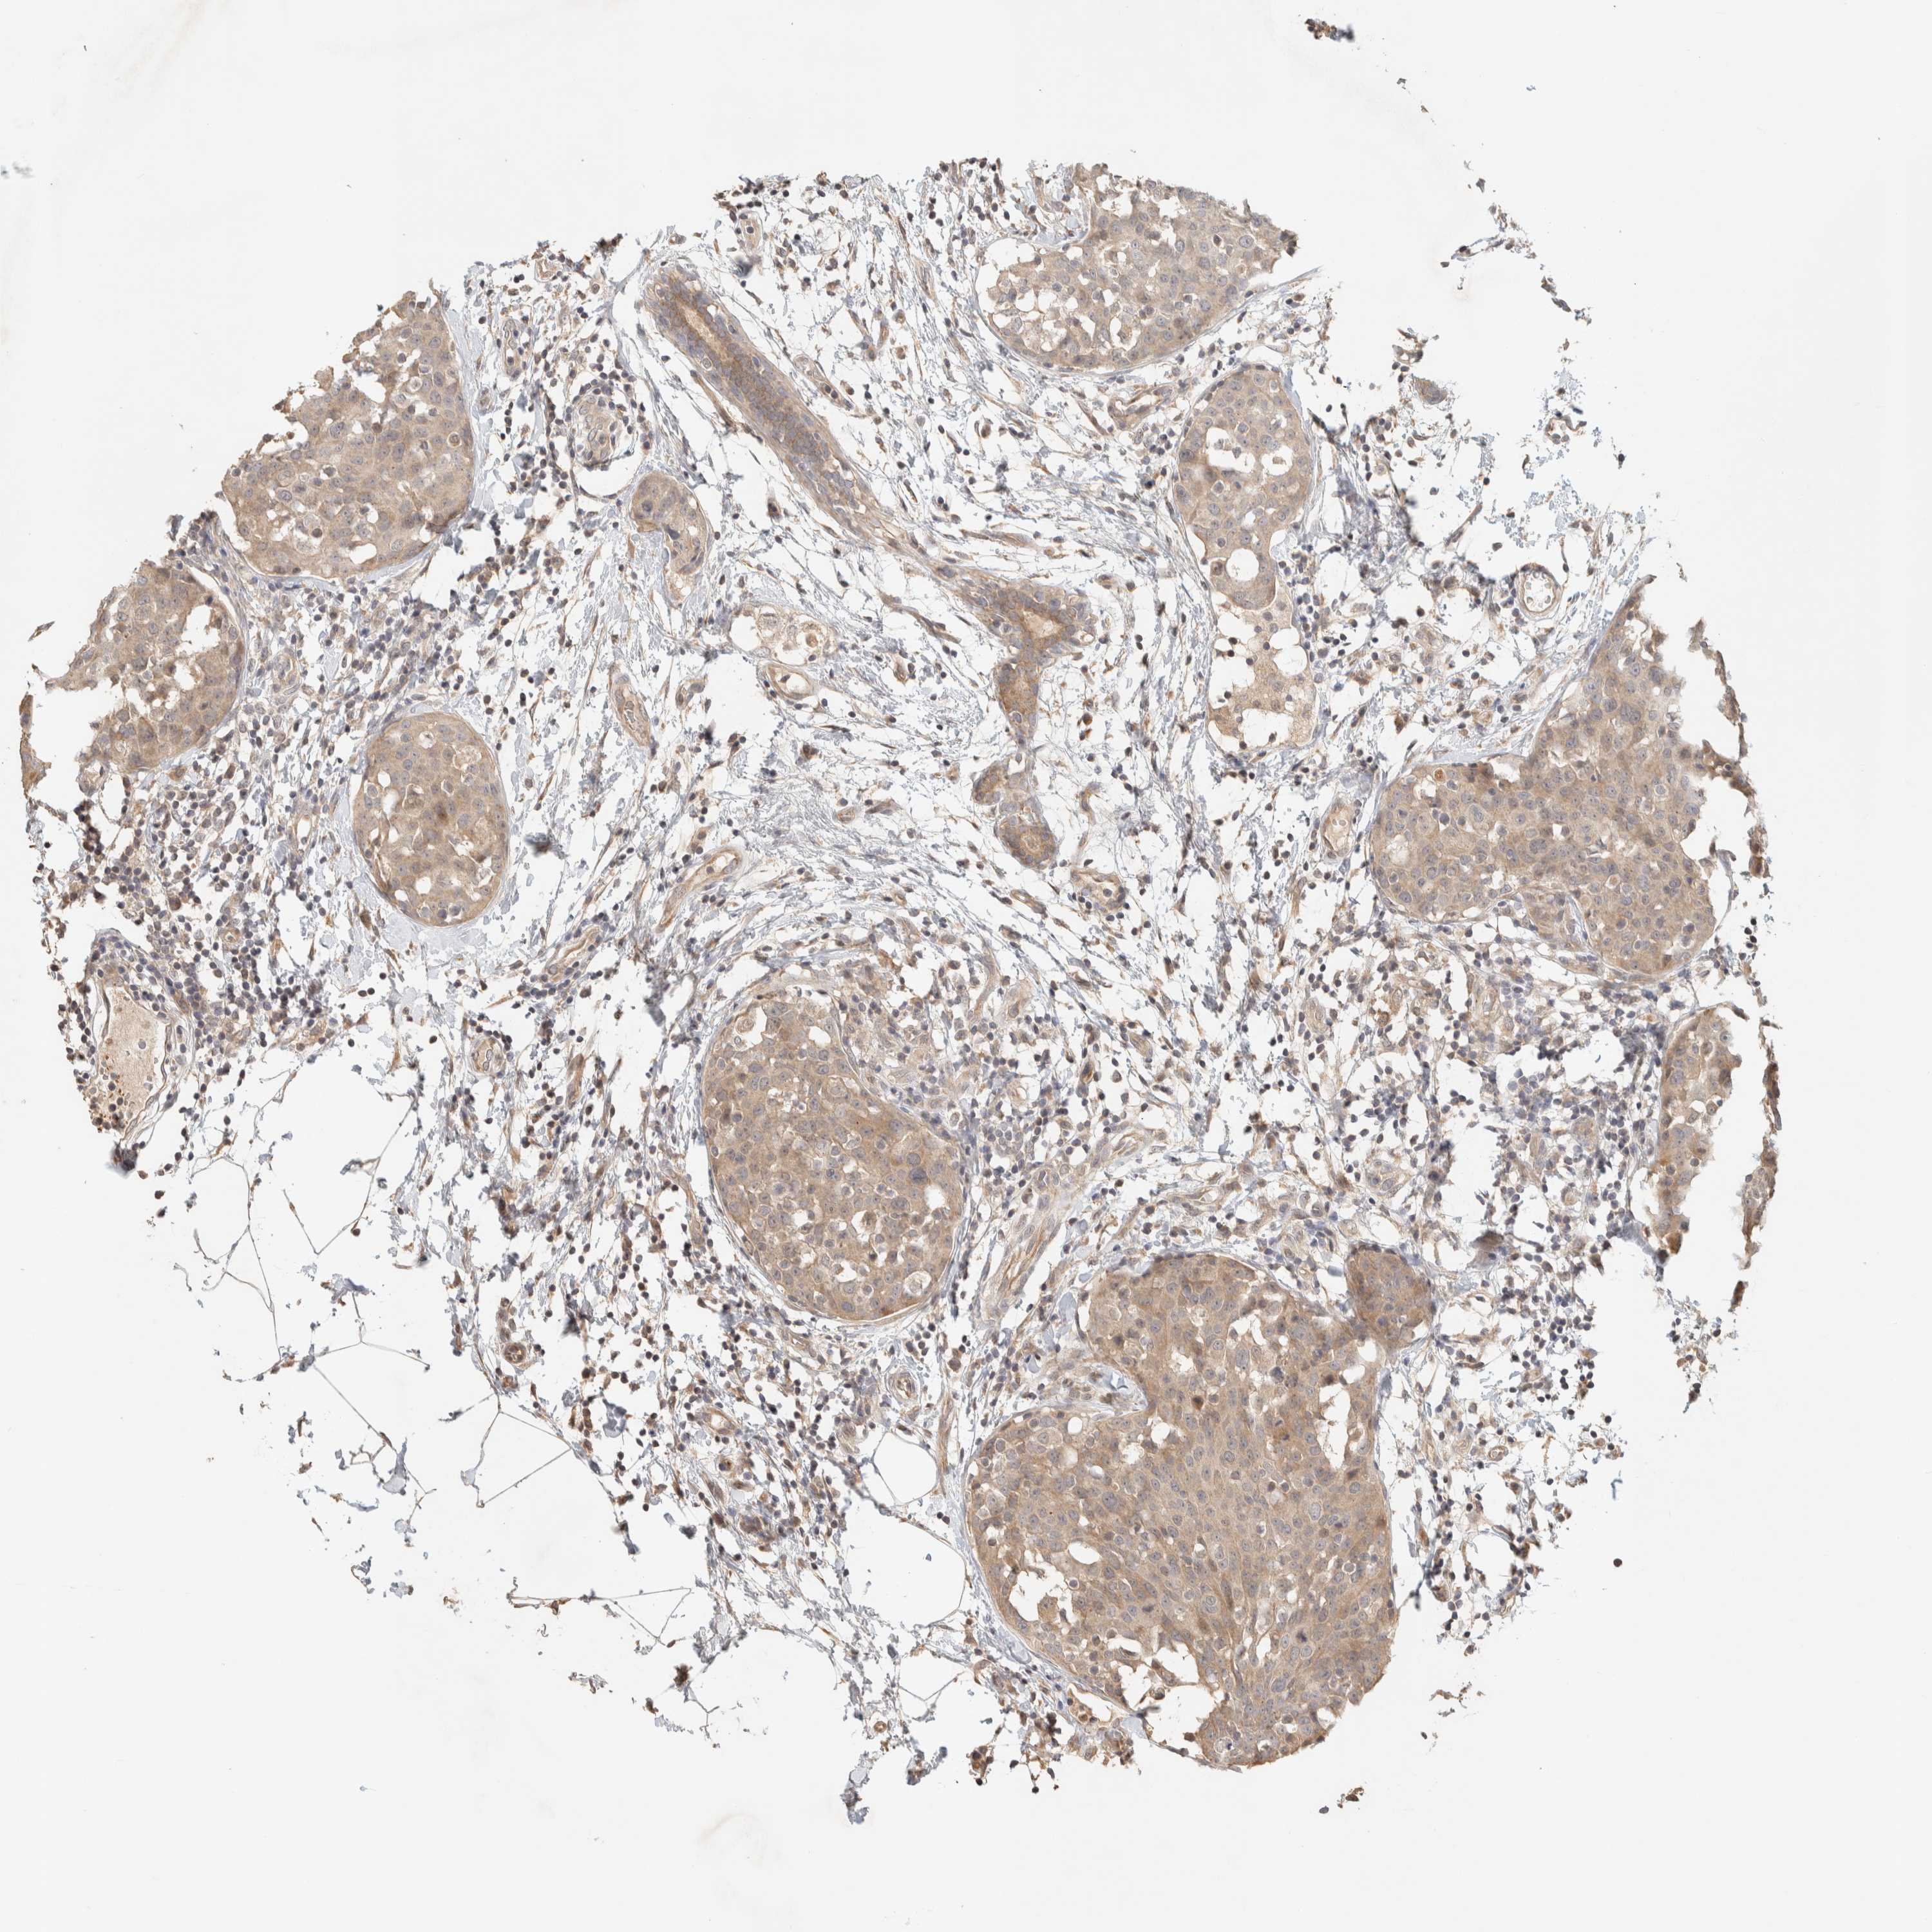

CANCER BREAST CANCER Show tissue menu

BRCA TCGA BRCA VALIDATION PROTEIN EXPRESSION

ANTIBODIES

AND

VALIDATION